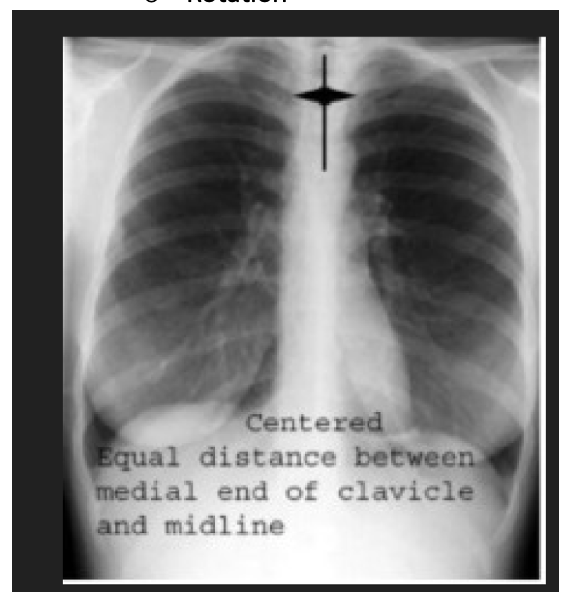

rotation on X-ray

central trachea and equal distance between medial end of clavicle and midline